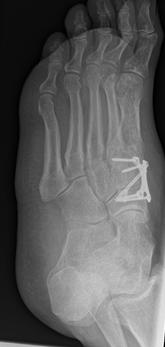

4.- 06/2017 nach Rearthrodese

Die Stabilisierung erfolgte nunmehr mittels Platte und einer externen Zugschraube. Es wurde wiederum Knochenersatzmaterial angelagert.